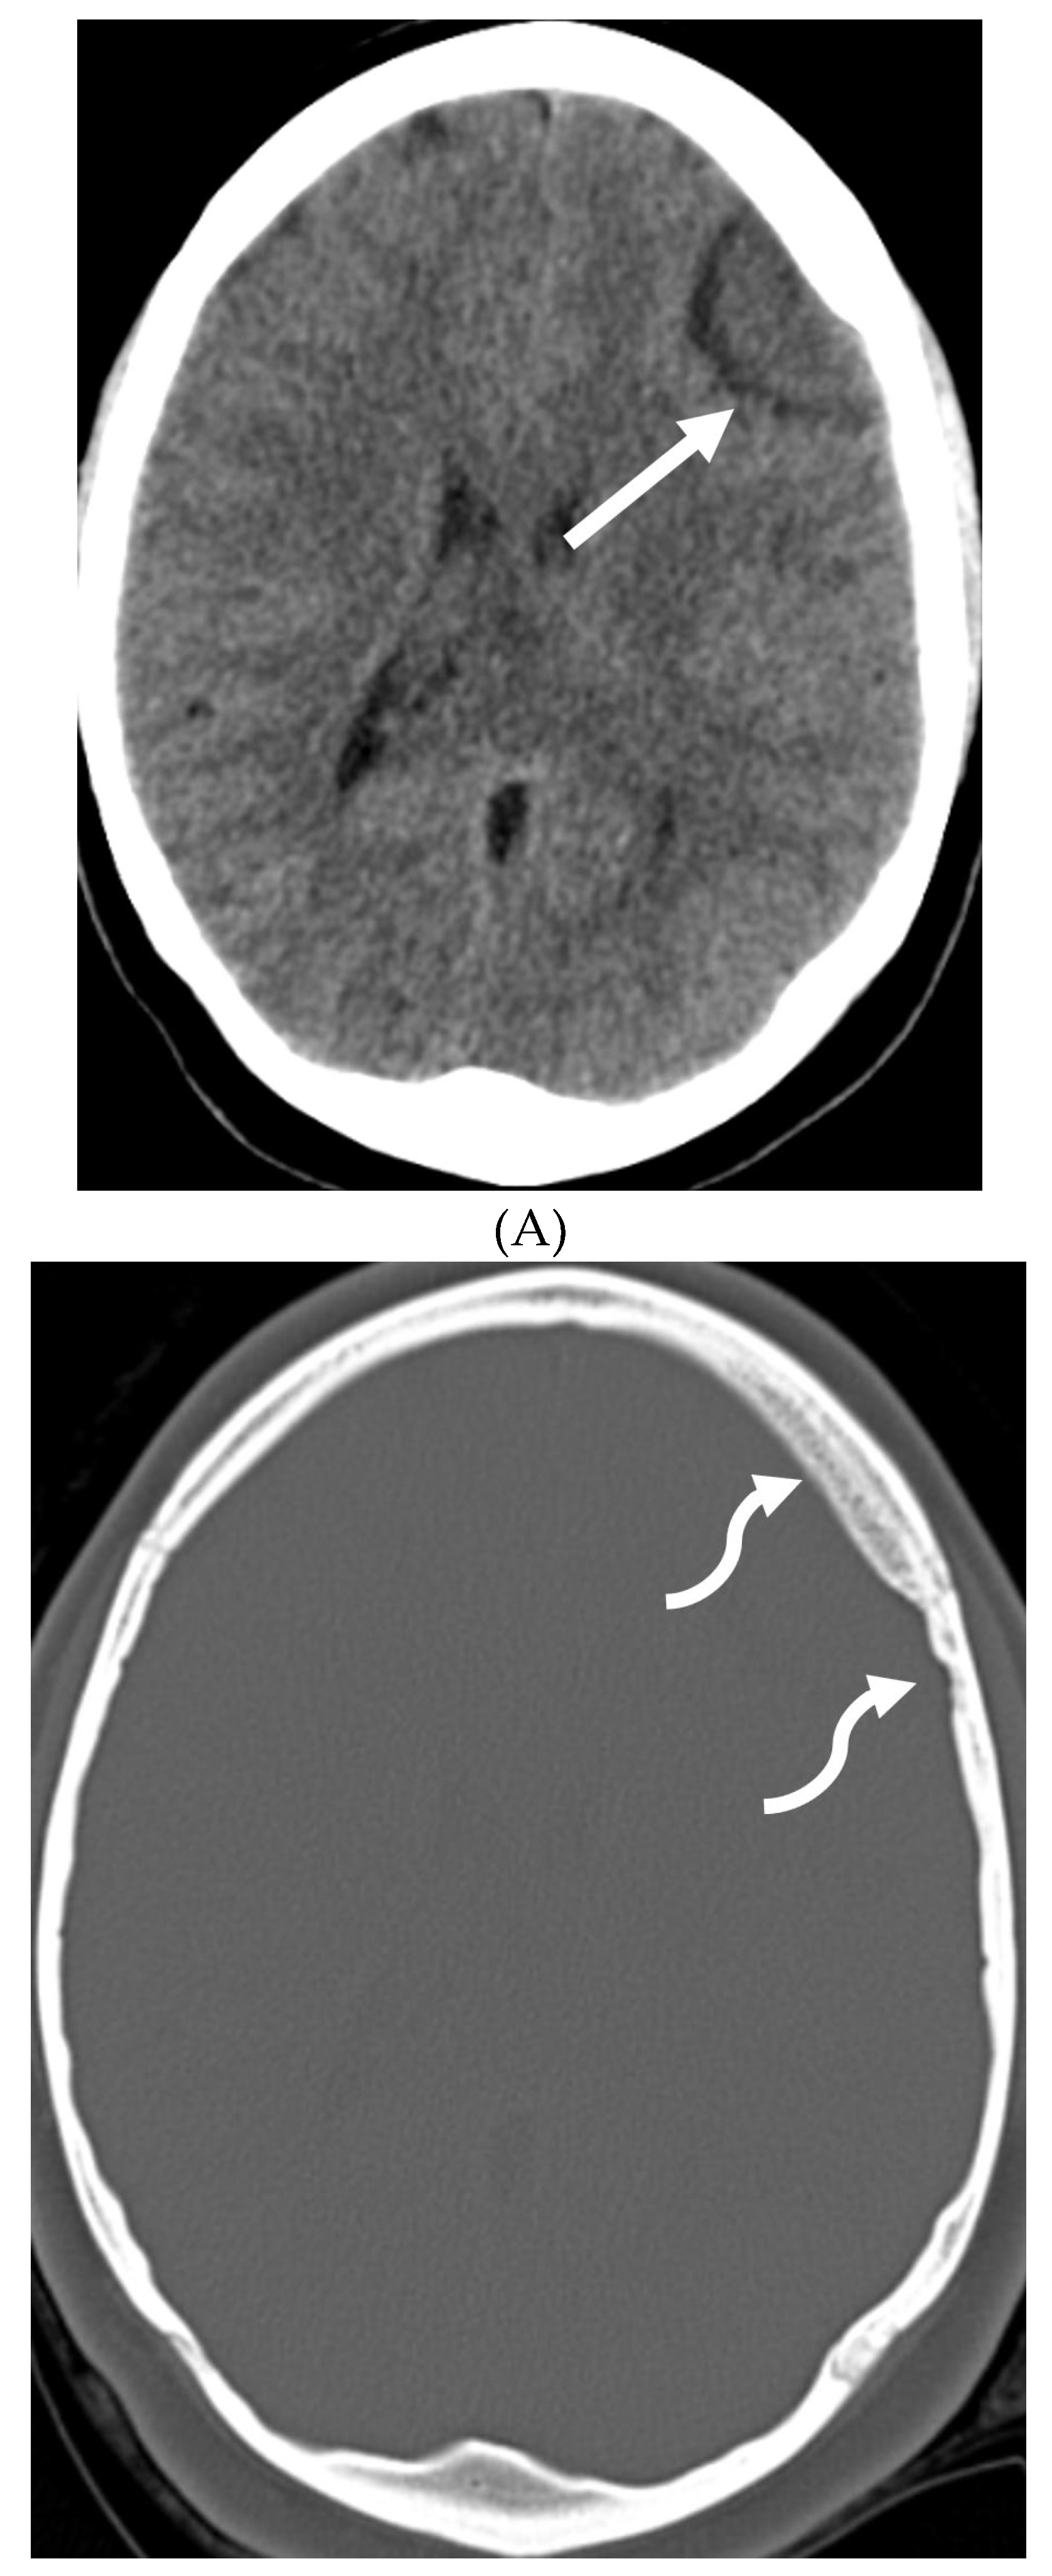

- Shah LM, McLean LA, Heilbrun ME, Salzman KL. Intracranial hypotension: improved MRI detection with diagnostic intracranial angles. AJR Am J Roentgenol. 2013 Feb;200(2):400-7. PMID: 23345364. [CrossRef]

- Yuh EL, Dillon WP. Intracranial hypotension and intracranial hypertension. Neuroimaging Clin N Am. 2010 Nov;20(4):597-617. PMID: 20974378. [CrossRef]

- Medina JH, Abrams K, Falcone S, Bhatia RG. Spinal imaging findings in spontaneous intracranial hypotension. AJR Am J Roentgenol. 2010 Aug;195(2):459-64. PMID: 20651205. [CrossRef]